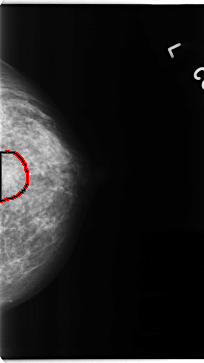

C_0153_1.LEFT_MLO

LEFT_MLO LINES 4704 PIXELS_PER_LINE 2456 BITS_PER_PIXEL 12 RESOLUTION 50 OVERLAY

FILE: C_0153_1.LEFT_MLO.OVERLAY

TOTAL_ABNORMALITIES 1

ABNORMALITY 1

LESION_TYPE MASS SHAPE LOBULATED MARGINS ILL_DEFINED

ASSESSMENT 4

SUBTLETY 4

PATHOLOGY MALIGNANT

TOTAL_OUTLINES 1

BOUNDARY